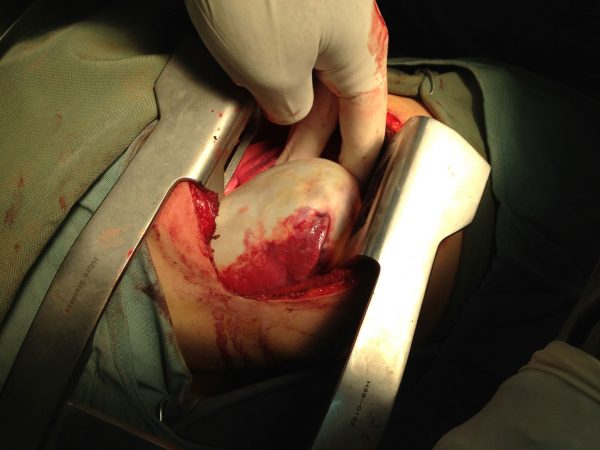

جراحی کيست هيداتيد ريه به روش تخليه